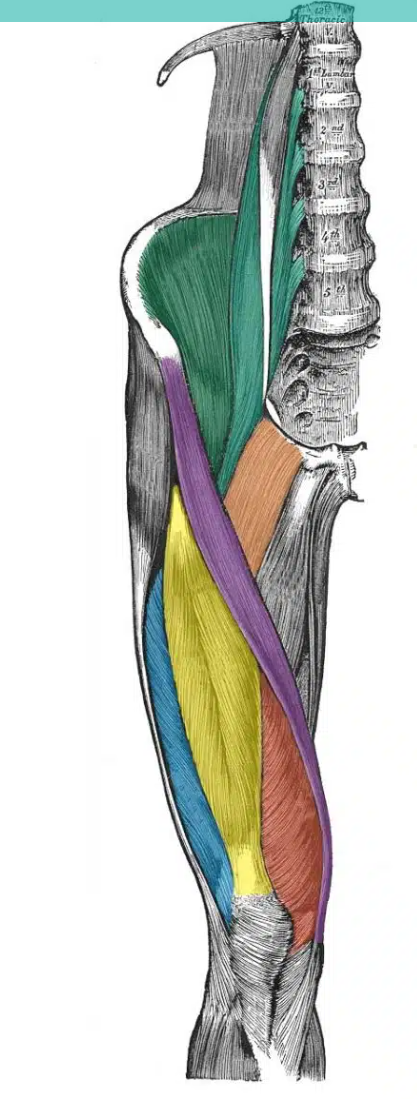

green vertical muscle- close to spine

psoas major

green muscle - in the iliac fossa

iliacus

12

yellow

rectus femoris

13

red

vastus medialis

14

blue

vastus lateralis

15

purple

sartorius

16

orange

pectineus